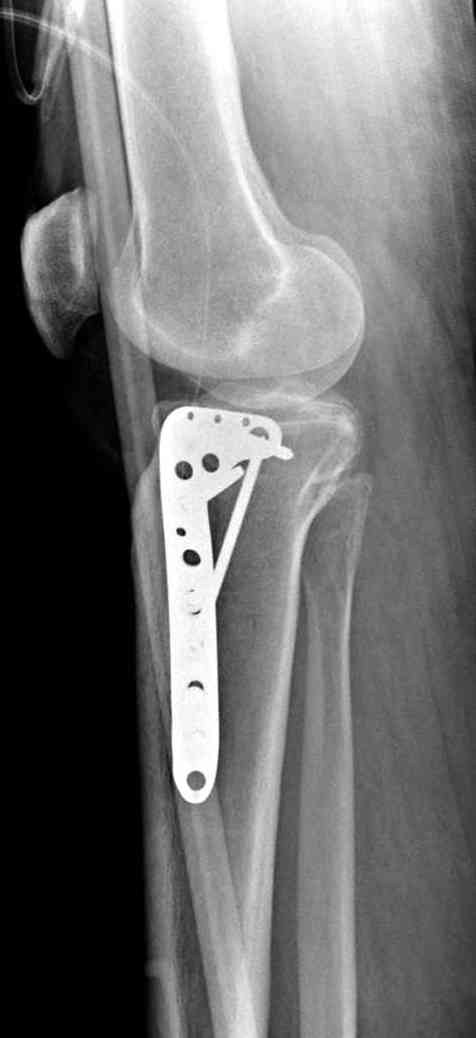

Это техника применяется, когда имеется

центральная импрессия, а при ипрессии с краевым переломом - после приподнимания импрессии опорная (Butress) пластина, как на снимке.